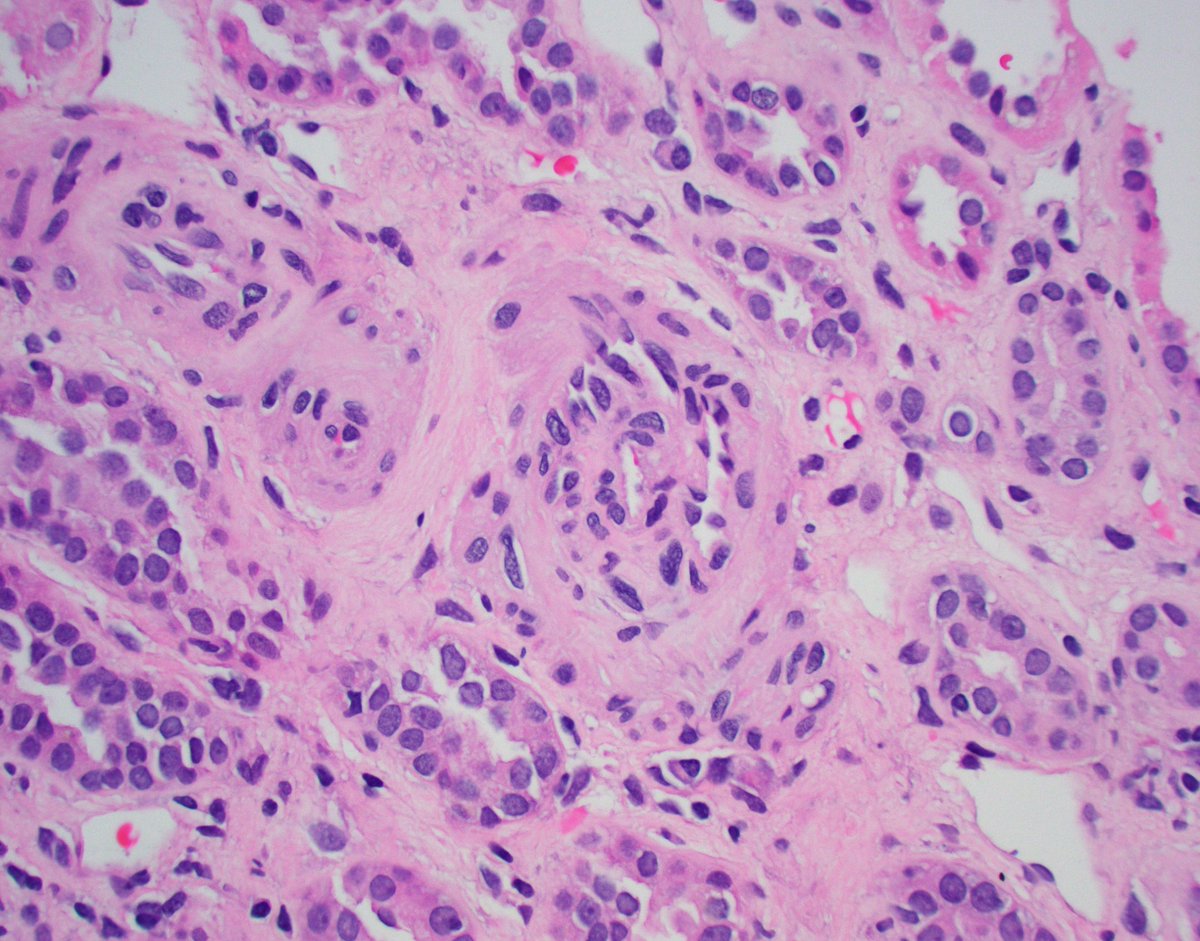

Unfortunate but not rare IgAN presentation. Pt in their 30's, no PMHx, presented with HTN emergency, CKD, hematuria, proteinuria. Advanced IgAN with severe IFTA, focal active crescents (M1 E1 S1 T2 C1). Wish we could catch these cases earlier. #renalpath #pathtwitter #nephrology